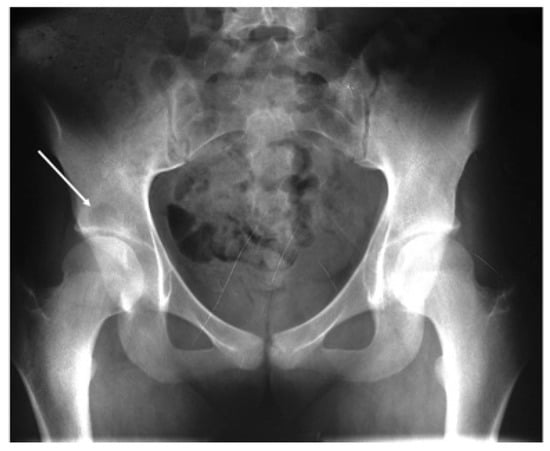

2. Case Presentation